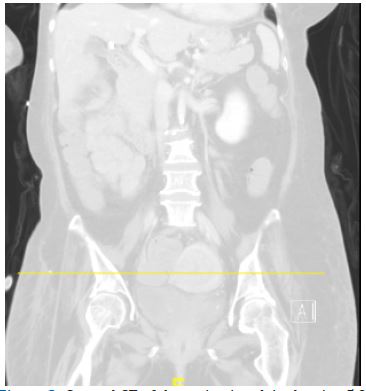

The clinical photograph (Figure 1) depicts multiple warty, raised lesions with a ‘stuck-on’ appearance, on the patient’s back. She had a history of a previous spinal cord tumor. A serum CA-125 was raised, and a Computed Tomography scan found a suspicious-looking heterogenous 5.9 cm uterine mass corresponding histologically to endometrial cancer (Figures 2 & 3).

Figure 3: Coronal CT of the patient’s pelvis showing 5.9 cm heterogenous uterine mass.

Figure 2: Axial CT of the patient’s pelvis showing 5.9 cm heterogenous uterine mass.